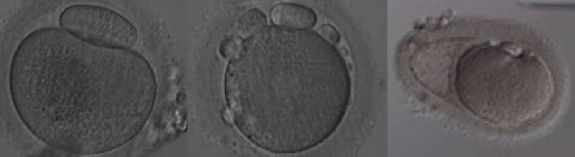

二、异常卵子的形态

在促排卵周期,一批获卵中总会有少数几个形态异常的卵子,漂亮的卵子千篇一律,异常的卵子各有各的异常。我们根据异常的类型分为胞浆外形态异常和胞浆内形态异常。目前的观点认为,卵子的轻微异常并不会影响到胚胎的发育潜力,严重的异常卵子才会影响胚胎的发育潜力。当然,这都是形态学的初步评价,成功妊娠并活产才是评价一个卵子质量的金标准。

(图:胞浆内形态异常)

(图:包浆外形态异常)